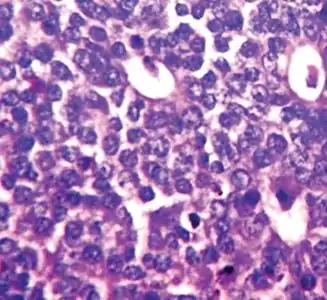

Mitotic count

This parameter assesses how many mitotic figures (dividing cells) the pathologist sees in 10x high power microscope field. One of the hallmarks of cancer is that cells divide uncontrollably. The more cells that are dividing, the worse the cancer.

Note: Mitotic figures are counted only at the periphery of the tumor, and counting should begin in the most mitotically active areas.